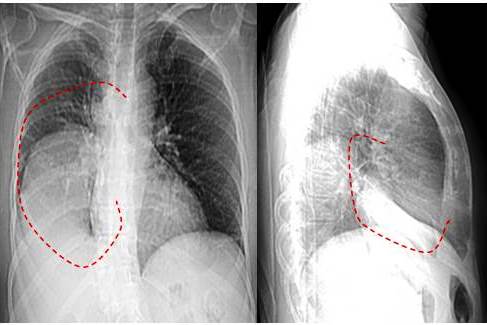

Los exámenes complementarios realizados mostraron los siguientes resultados: hemoglobina: 12 g/L, velocidad de sedimentación globular: 22 mm/h, LDH: 201 mmol/L. Los estudios de imágenes: en la radiografía de tórax se observa imagen redondeada densa homogénea que ocupa 2/3 del hemitórax derecho, con desplazamiento del mediastino hacia el lado opuesto con rechazo y compresión de las estructuras cardiomediastinales y del pulmón (atelectasia) (Figuras 1 A y B).

La tomografía computarizada de tórax reporta lesión de tejido blando ovalada de contorno parcialmente definidos con contacto pleural, la cual mide 9,8 cm x 8,5 cm, con engrosamiento intersticial difuso bilateral con bandas atelectásicas en el lóbulo inferior. Lesión nodular de 1 cm ubicada en el lóbulo medio (Figura 2). La tomografía de abdomen no reveló ni lesión ocupante de espacio ni enfermedad metastásica.